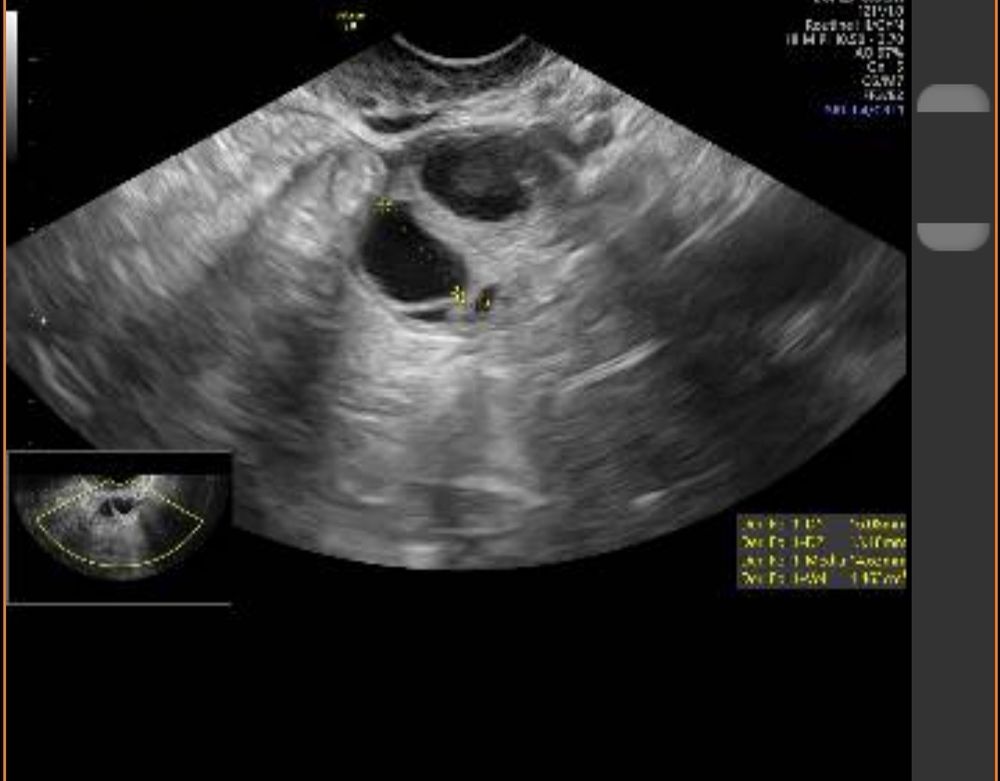

Жт или лютинизация фоликула?

Скоро два раза мама!!!))), ну у меня 1 дпо получается 20 мм. У меня лопаются 22-24 мм, на 4 дпо уже 26. Ну я так понимаю жт и лютинизированый фоликул трудно отличить. Надо сразу в день О смотреть. Просто на 1 дпо мне вообще левый врач смотрел.

Мила, у меня как-то в цикле стимуляции непонятки тоже были с УЗИ. В итоге пошла на экспертное УЗИ, дороговато конечно чем обычно, но хоть все по полочкам разложили. В итоге было 1 ЖТ, 1 лютеинизировавшийся фолликул и 1 в регресс ушел. По изображению лютеинизировавшийся фолликул и ЖТ очень похожи по мне, но врачи их как-то различают по кровотоку, содержимому и т.д.